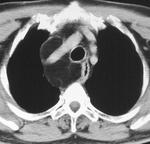

Рис.Слева - обзорная рентгенограмма органов грудной клетки пациента с внутригрудным зобом, по центру - компьтерная томограмма этого же пациента (стрелками указан внутригрудной зоб), справа - сцинтиграфия щитовидной железы у пациента с загрудинным зобом (желтой стрелкой указан холодный загрудинный узел, красной - горячий узел в верхнем полюсе правой доли щитовидной железы)